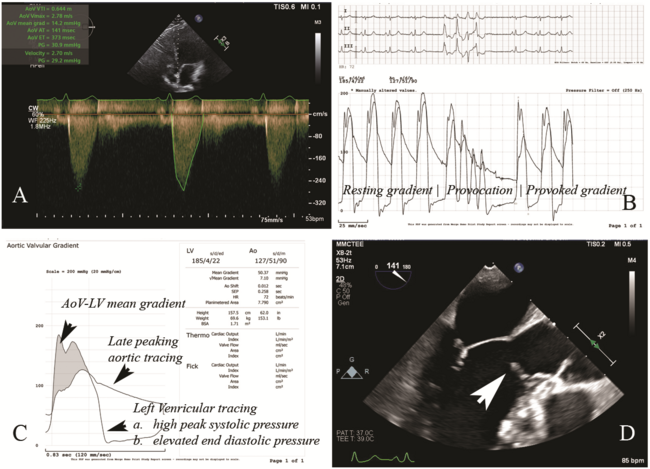

A 42-year-old woman who underwent subaortic membrane surgical resection in 2014 presented with severe dyspnea and recent syncope. Evaluation in the emergency room revealed stable vital signs and unremarkable electrocardiogram and cardiac biomarkers. Transthoracic echocardiogram showed an aortic valve (AoV) peak velocity of 2.78 m/s, a peak gradient (PG) of 31 mm Hg, a mean gradient of 14 mm Hg, and an AoV area of 2.09 cm² (Figure A). There were elevated pressure gradients across the LVOT and AoV, with a PG of 31 mm Hg at rest.

Regrowth of subaortic membrane was suspected given the normal AoV morphology and elevated gradients. Cardiac catheterization demonstrated normal coronary arteries, but an elevated left ventricular end-diastolic pressure at 30 mm Hg. Resting and provoked LVOT gradient were elevated at 20 and 50 mm Hg, respectively (Figure B and C). Transesophageal echocardiogram (TEE) revealed regrowth of subaortic membrane in the LVOT (Figure D). Video 1 shows the mid-esophageal long-axis view through the LVOT and aortic valve. Additionally, Video 2 shows the mid-esophageal long-axis view through the LVOT and aortic valve; X-plane focused at the subaortic membrane and color flow Doppler is shown in Video 3.